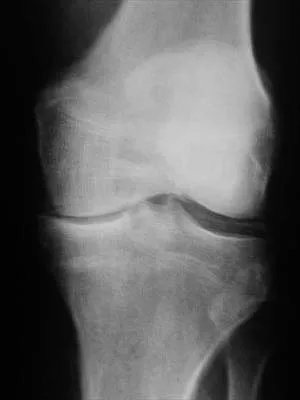

Figure 40 shows the AP radiograph of a 55-year-old man who reports left knee pain. Which of the following conditions is least likely to produce this radiographic presentation?

The radiograph reveals densities within the articular cartilage of the knee commonly referred to as chondrocalcinosis. The term chondrocalcinosis refers to the presence of calcium-containing crystals detected as radiodensities in cartilage. Calcium-containing crystals other than calcium pyrophosphate dihydrate may also deposit in articular cartilage and menisci, producing both radiographically detectable densities in cartilage and joint inflammation or degeneration. Hemochromatosis, alkaptonuria (ochronosis), and Wilson's disease are characterized by cellular deposition of iron, calcium, and copper ions, respectively, into various tissues including articular cartilage and can give this appearance. Septic arthritis does not usually cause chondrocalcinosis. Klippel JH (ed): Primer on the Rheumatic Diseases, ed 11. Atlanta, GA, Arthritis Foundation, 1997, pp 226-229 and 328-331.